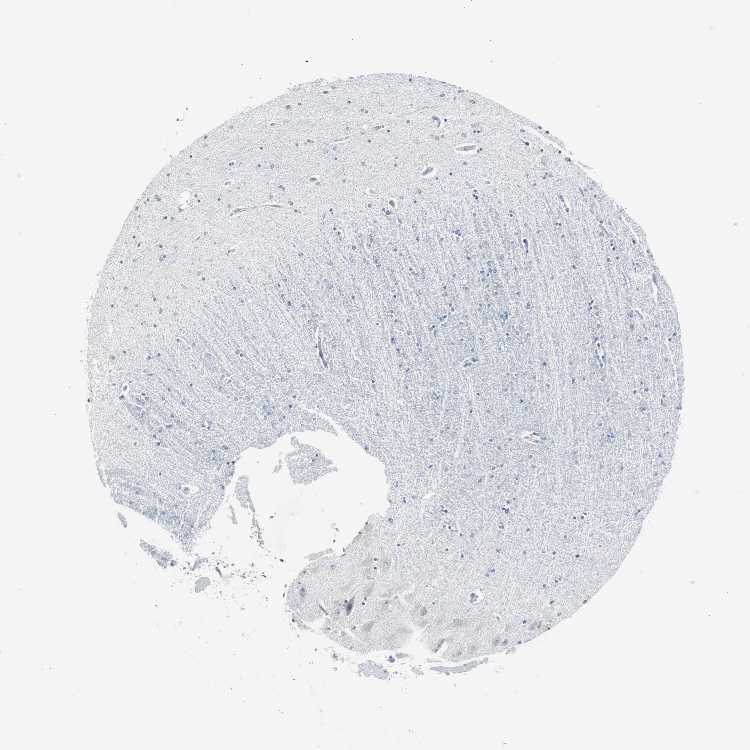

HIPPOCAMPUS - Antibody stainingi

Antibody staining in the annotated cell types in the current human tissue is reported as not detected, low, medium, or high, based on conventional immunohistochemistry profiling in selected tissues. This score is based on the combination of the staining intensity and fraction of stained cells.

Each image is clickable and will lead to virtual microscopy that enables deeper exploration of all samples and also displays staining intensity scores, fraction scores and subcellular localization as well as patient and tissue information for each sample.

Antibody HPA006159Antibody CAB009382

Glial cells Not detectedNot detected

Neuronal cells Not detectedLow